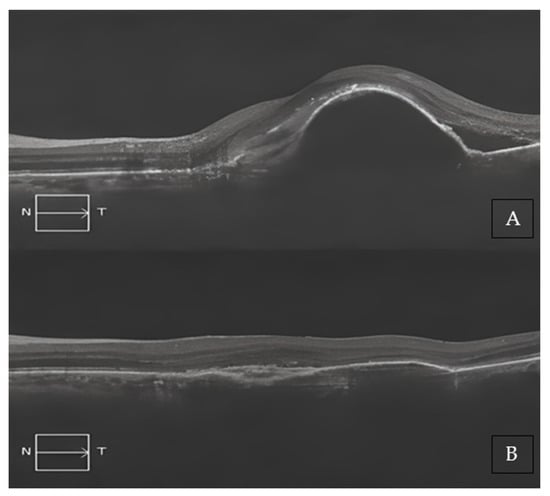

Only one 78-year-old treatment-naïve male with no previous history of systemic inflammatory diseases experienced an acute onset of anterior and intermediate uveitis, which occurred about 15 days after the second loading phase injection. The patient presented with diffuse inflammatory cells and flare within the anterior chamber and keratic endothelial precipitates, along with a significant vitreous haze. His BCVA prior to this event was 0.44 LogMar, which sharply dropped to 1.00 LogMar secondary to the uveitis. The patient was promptly started on a treatment regimen with high doses of topical and systemic steroids and mydriatic eye drops, achieving a significant improvement in the entire clinical picture after only 20 days from the start of therapy (Figure 4A–D). Eventually, the patient fully recovered, as confirmed by the full restoration of BCVA to 0.44 LogMar and the complete disappearance of any overmentioned uveitic clinical feature. Brolucizumab injections were continued as per protocol, and a strict observation was agreed with the patient, who did not show any recurrence or new onset of inflammatory adverse events.

Figure 4. Adverse event of anterior and intermediate uveitis in a 78-year-old treatment-naïve patient. (A) Baseline SD-OCT scan acquired with Maestro 3D OCT-1 (Topcon Corporation, Tokyo Japan) prior to the therapy with Brolucizumab displaying hyper-iso-reflective subretinal material distorting the retinal profile, RPE irregularities, and both IR and SR edema. BCVA at this stage was 1.00 LogMAR. (B) SD-OCT at the end of the loading phase showed a striking retinal profile restoration with an important reduction in the hyper-iso-reflective subretinal material and both the IR and SR edema. BCVA significantly improved to 0.44 LogMAR. (C) Two weeks after the second injection, an anterior and intermediate uveitis with massive vitreous haze occurred with difficulty in exploring the ocular fundus. Diffuse inflammatory cells and flare within the anterior chamber, and keratic endothelial precipitates, were also noted. BCVA dramatically dropped to 1.0 LogMAR. (D) Three weeks after therapy with high doses of topical and systemic steroids and mydriatic eye drops, a significant improvement in the entire clinical picture was achieved. Eventually, the uveitis totally resolved with a full restoration of BCVA back to 0.44 LogMAR and the complete disappearance of any uveitis clinical finding.